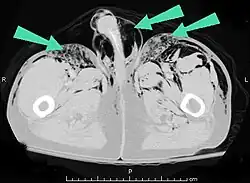

O enfisema pode produzir protuberâncias, como nódulos móveis com ruídos crepitantes a palpação. Em uma radiografia de tórax, o enfisema subcutâneo pode ser visto como estriações radioluzentes (escuras) nas áreas com músculos. O ar nos tecidos subcutâneos pode interferir na radiografia do tórax, potencialmente obscurecendo condições graves, como o pneumotórax. Também pode reduzir a eficácia do ultrassom.[8] Também é visível na tomografia e na ressonância magnética como bolhas escuras.

O enfisema subcutâneo é geralmente benigno.[1] Na maioria das vezes, o próprio enfisema não precisa de tratamento (embora as condições a partir das quais ele resulta precisem); no entanto, se a quantidade de ar for grande, isso pode interferir na respiração e ser desconfortável.[9] Quando a quantidade de ar expelida das vias aéreas ou do pulmão se torna enorme, geralmente devido à ventilação com pressão positiva , as pálpebras incham tanto que o paciente não consegue enxergar. Além disso, a pressão do ar pode impedir o fluxo sanguíneo para a aréola da mama e pele do escroto ou dos lábios. Isso pode levar à necrose da pele nessas áreas. Estas são situações urgentes que requerem descompressão rápida e adequada.[10][11][12] Casos graves podem comprimir a traquéia e requerem tratamento.[13]